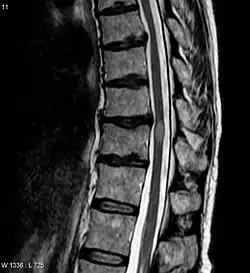

- MRT-Untersuchung des Rückenmarks (Kernspintomographie)